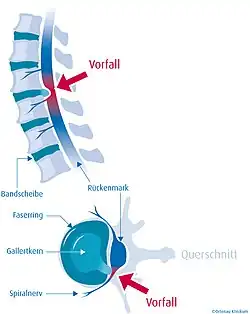

Der Bandscheibenvorfall (lateinisch Prolapsus nuclei pulposi, ärztlich oft Nucleus-pulposus-Prolaps, kurz NPP), auch Bandscheibenprolaps (BSP), Bandscheibenhernie, Discushernie (oder Diskushernie) und Discusprolaps, ist eine Erkrankung der Wirbelsäule, bei der Teile der Bandscheibe in den Wirbelkanal – den Raum, in dem das Rückenmark liegt – vortreten. Im Gegensatz zur Bandscheibenprotrusion (Vorwölbung) wird beim Prolaps der Faserknorpelring der Bandscheibe (Anulus fibrosus) ganz oder teilweise durchgerissen, während das hintere Längsband (Ligamentum longitudinale posterius) intakt bleiben kann (sogenannter subligamentärer Bandscheibenvorfall).

Bandscheiben sind bradytrophe Gewebe, das heißt, sie werden nicht direkt aus dem Blutkreislauf heraus mit Nährstoffen versorgt, sondern durch Diffusion. Hierbei spielen semipermeable Membranen, welche die Knorpelringe voneinander trennen, die entscheidende Rolle. Durch Scherkräfte können diese Membranen einreißen, wodurch sie ihre Funktion verlieren und die Bandscheibe nebst Gallertkern der Bandscheibe (Nucleus pulposus) austrocknet (black disc lesion). Wenn es zu einem Bandscheibenvorfall kommt, ist der Gallertkern praktisch nicht mehr in seiner ursprünglichen Form vorhanden. Der Bandscheibenvorfall entsteht also zumeist auf dem Boden einer langjährigen Vorschädigung der Bandscheibe. Der Gallertkern (ca. 80 % Wasser) besteht bei der gesunden Bandscheibe aus einem gallertigen, zellarmen Gewebe und übernimmt bei Belastung zusammen mit den Knorpelringen und den Membranen die Funktion einer hydraulischen Kugel („Wasserkissen“). Die Wirbelkörper und Bandscheiben vorne ermöglichen zusammen mit den kleinen Wirbelgelenken hinten („Facettengelenke“) die hohe Beweglichkeit der gesamten Wirbelsäule und ihre hohe Stabilität.